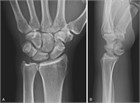

臨床像

舟状骨骨折は14~40歳に好発し,手関節を伸展した状態で手をついて転倒(FOOSH)し,関節可動域(ROM)の減少と手関節(特に橈側の背側)に強い痛みを訴える.身体診察では,変形や斑状出血はみられないが,動作や触診で疼痛を認め,しばしば腫脹もみられる.腫脹は特に解剖学的嗅ぎタバコ入れ(母指を伸展した際に,長母指外転筋と短母指伸筋の腱の間にある,手関節の橈側にみられる窪み.127.1)でみられる.疼痛は軽度のこともあるが,握ったり掴んだりすると悪化する.